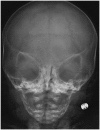

Cloverleaf Skull

A cloverleaf skull occurs when the cranium takes a shape similar to a cloverleaf, appearing trilobular, due to craniosynostosis (Fig. 3). It is a typical feature of various syndromes, and has been described for type I and II thanatophoric dysplasia, Boston type craniosynostosis, and others such as Carpenter syndrome, severe cases of Apert syndrome and Crouzon syndrome (4).

caption a8Cloverleaf skull sign.